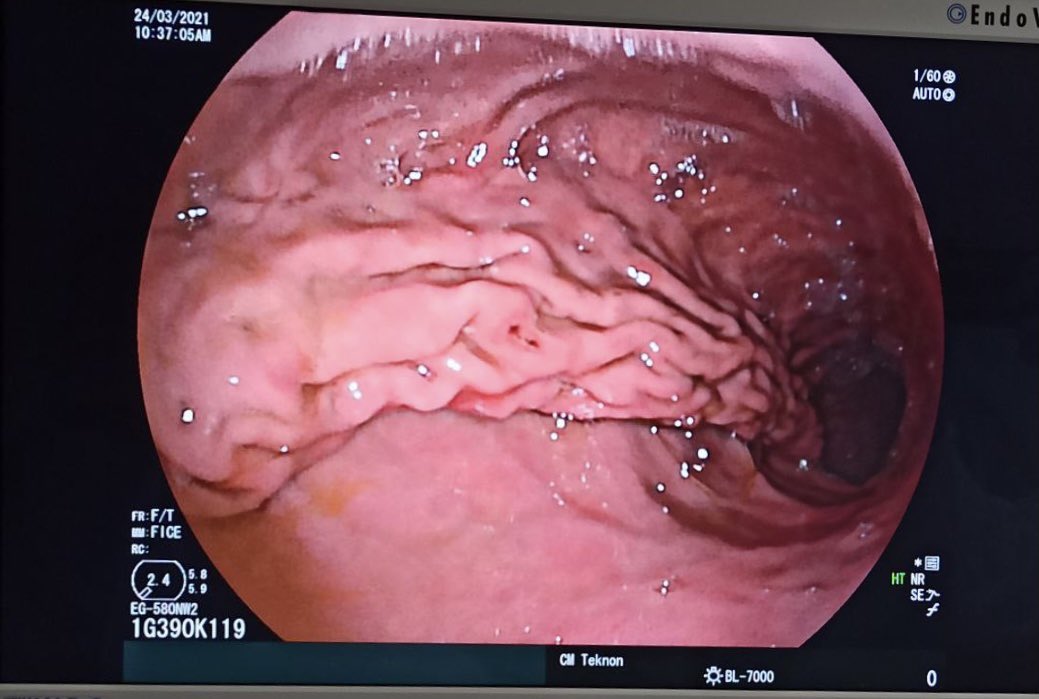

Os enseñamos uno de los procedimientos endoscópicos que hacemos en nuestra unidad. POEM (Per Oral Endoscopic Myotomy) para el tratamiento de la Acalasia #achalasia #endoscopytreatment #centromedicoteknon